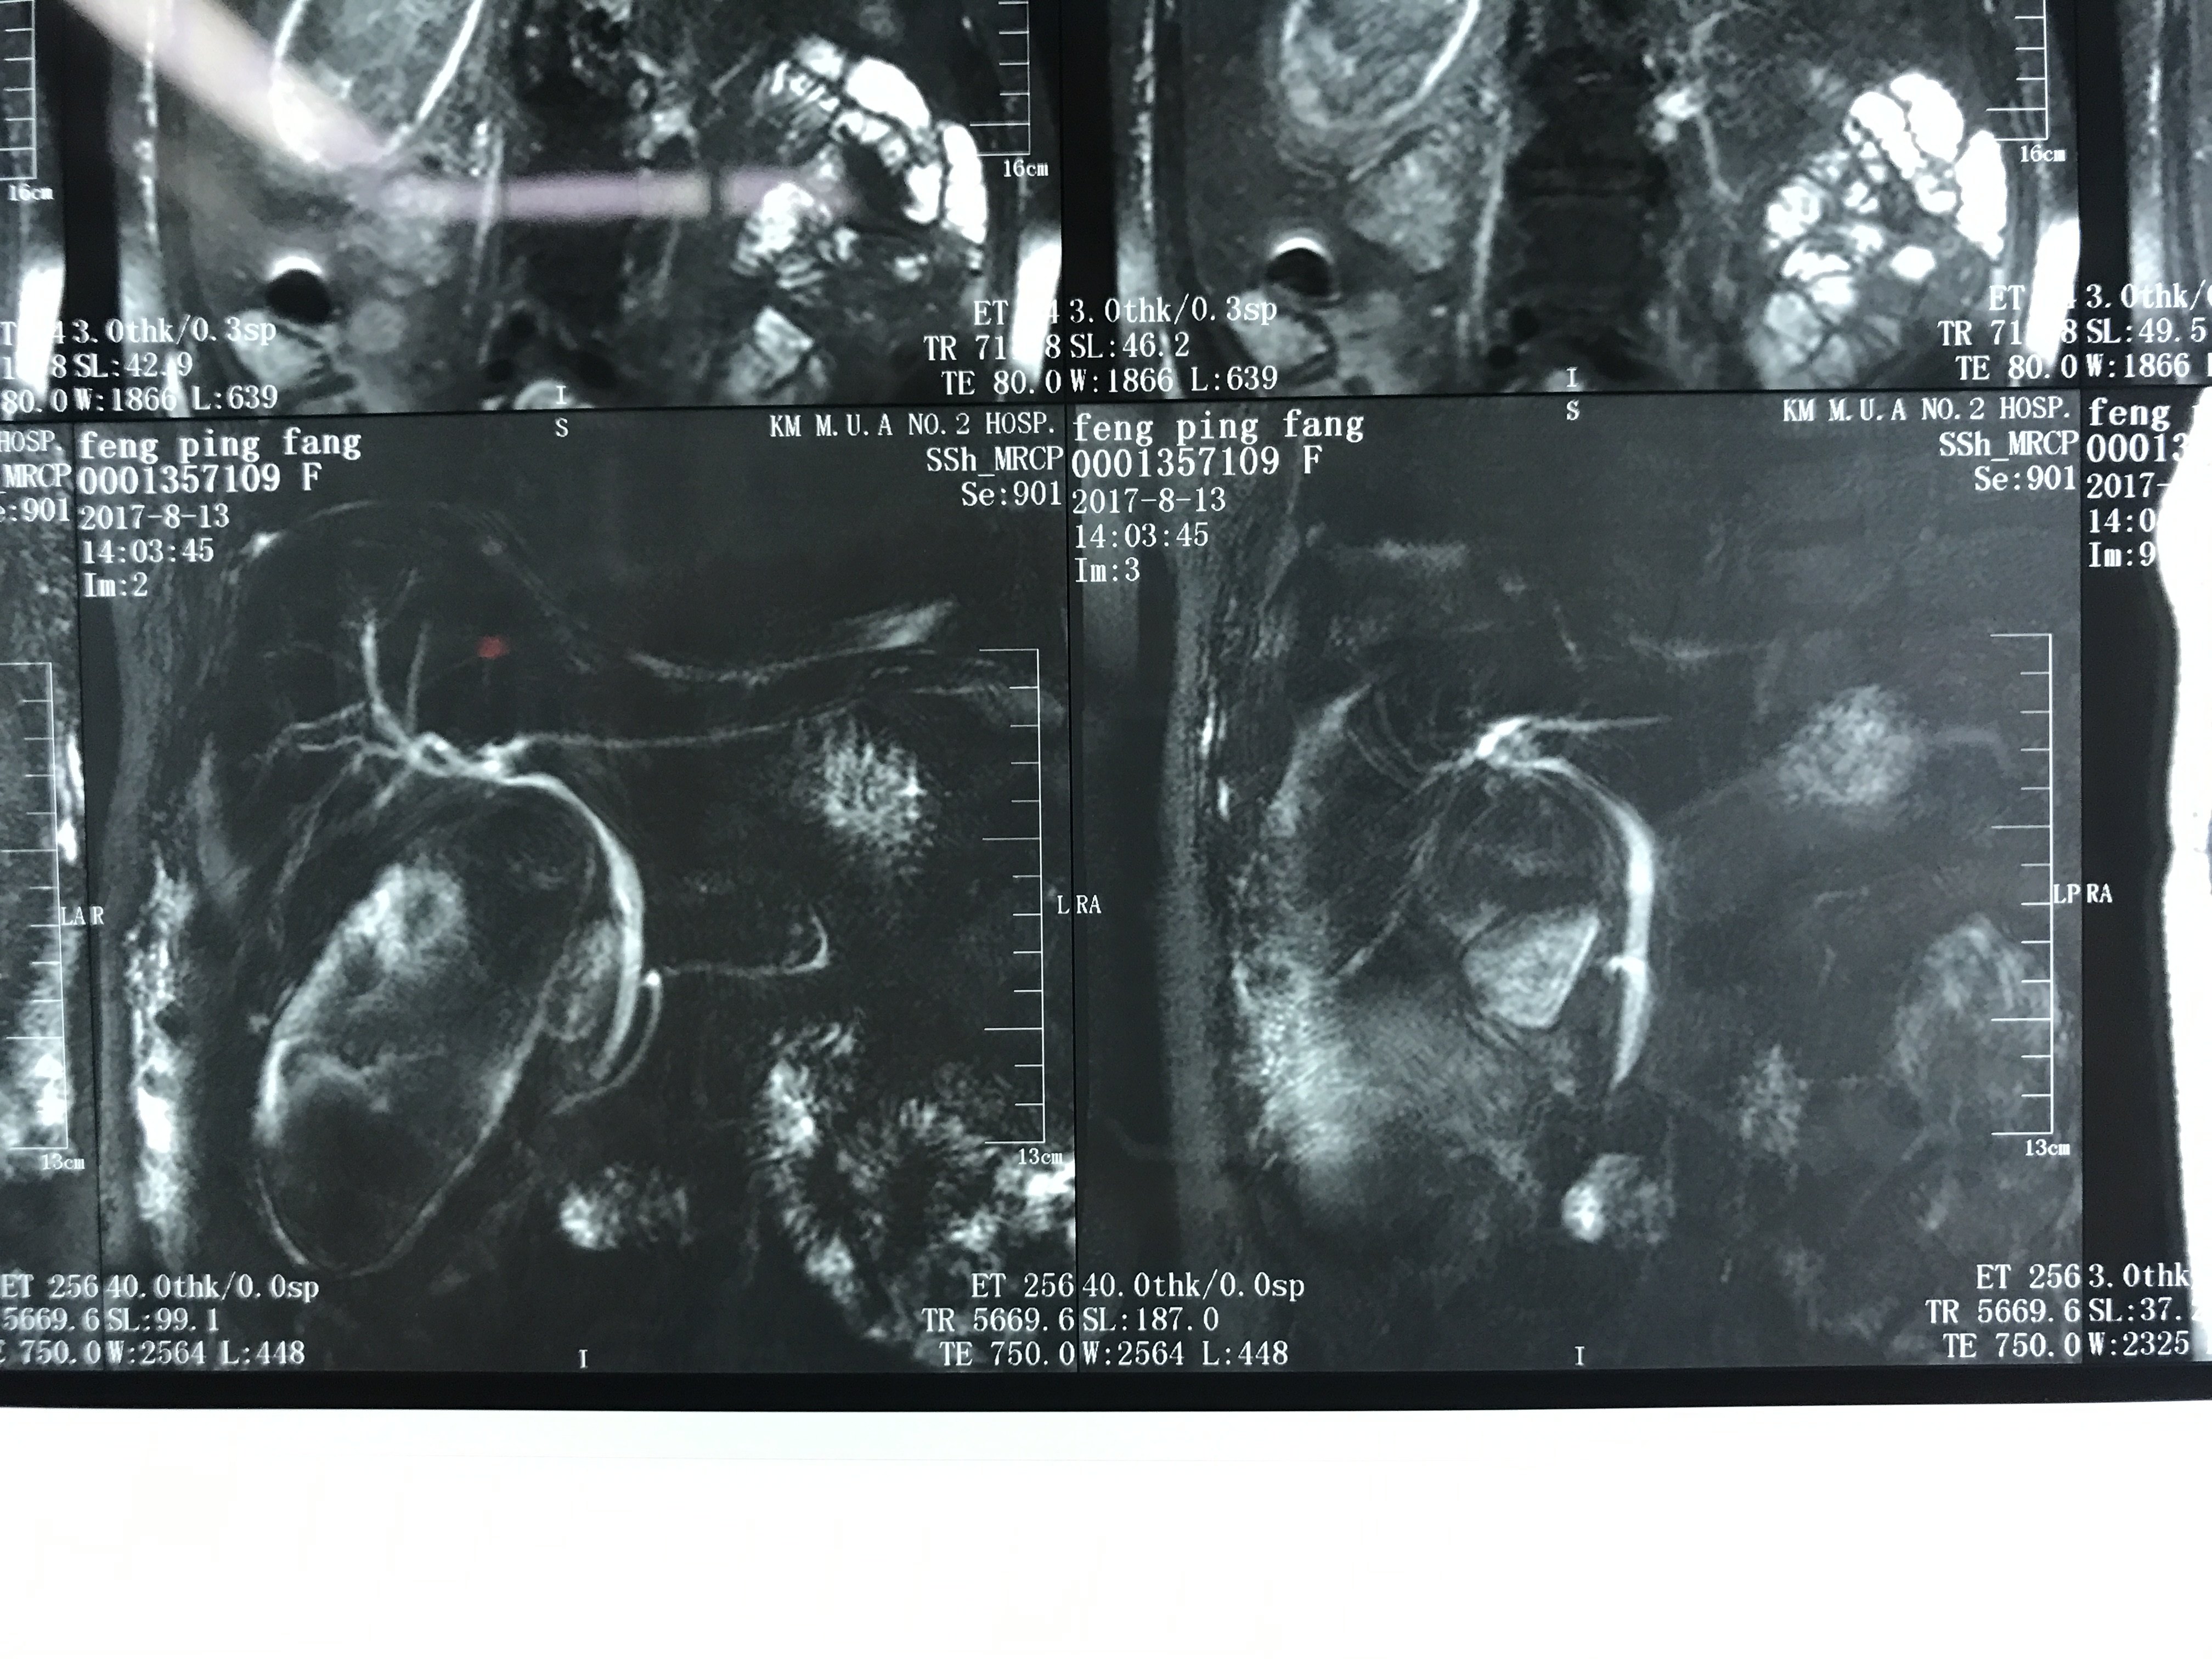

这里主要指的是CT、核磁共振等特殊检查的片子。

首先要解释的是一个是您拿到的影像片子,另一个是您拿到的报告单。

①报告单是放射科医生做出检查后给出的提示是总体性的且有一定法律效应的结论。

②我们专科医师看片子需要根据专科的角度去判断片子中疾患的部位、大小、血液供应、周围粘连、目前疾患的进展、甚至手术方案、病情的预后都已经了然在心中了。

所以完整的把检查资料传到医生的手中是非常关键的。

如何正确的把拍的片子发给医生看!

一般的报告就不再说了,正常拍摄就可以,我说的是片子应该怎么拍,一般是1-4小张拍一次,如下图: